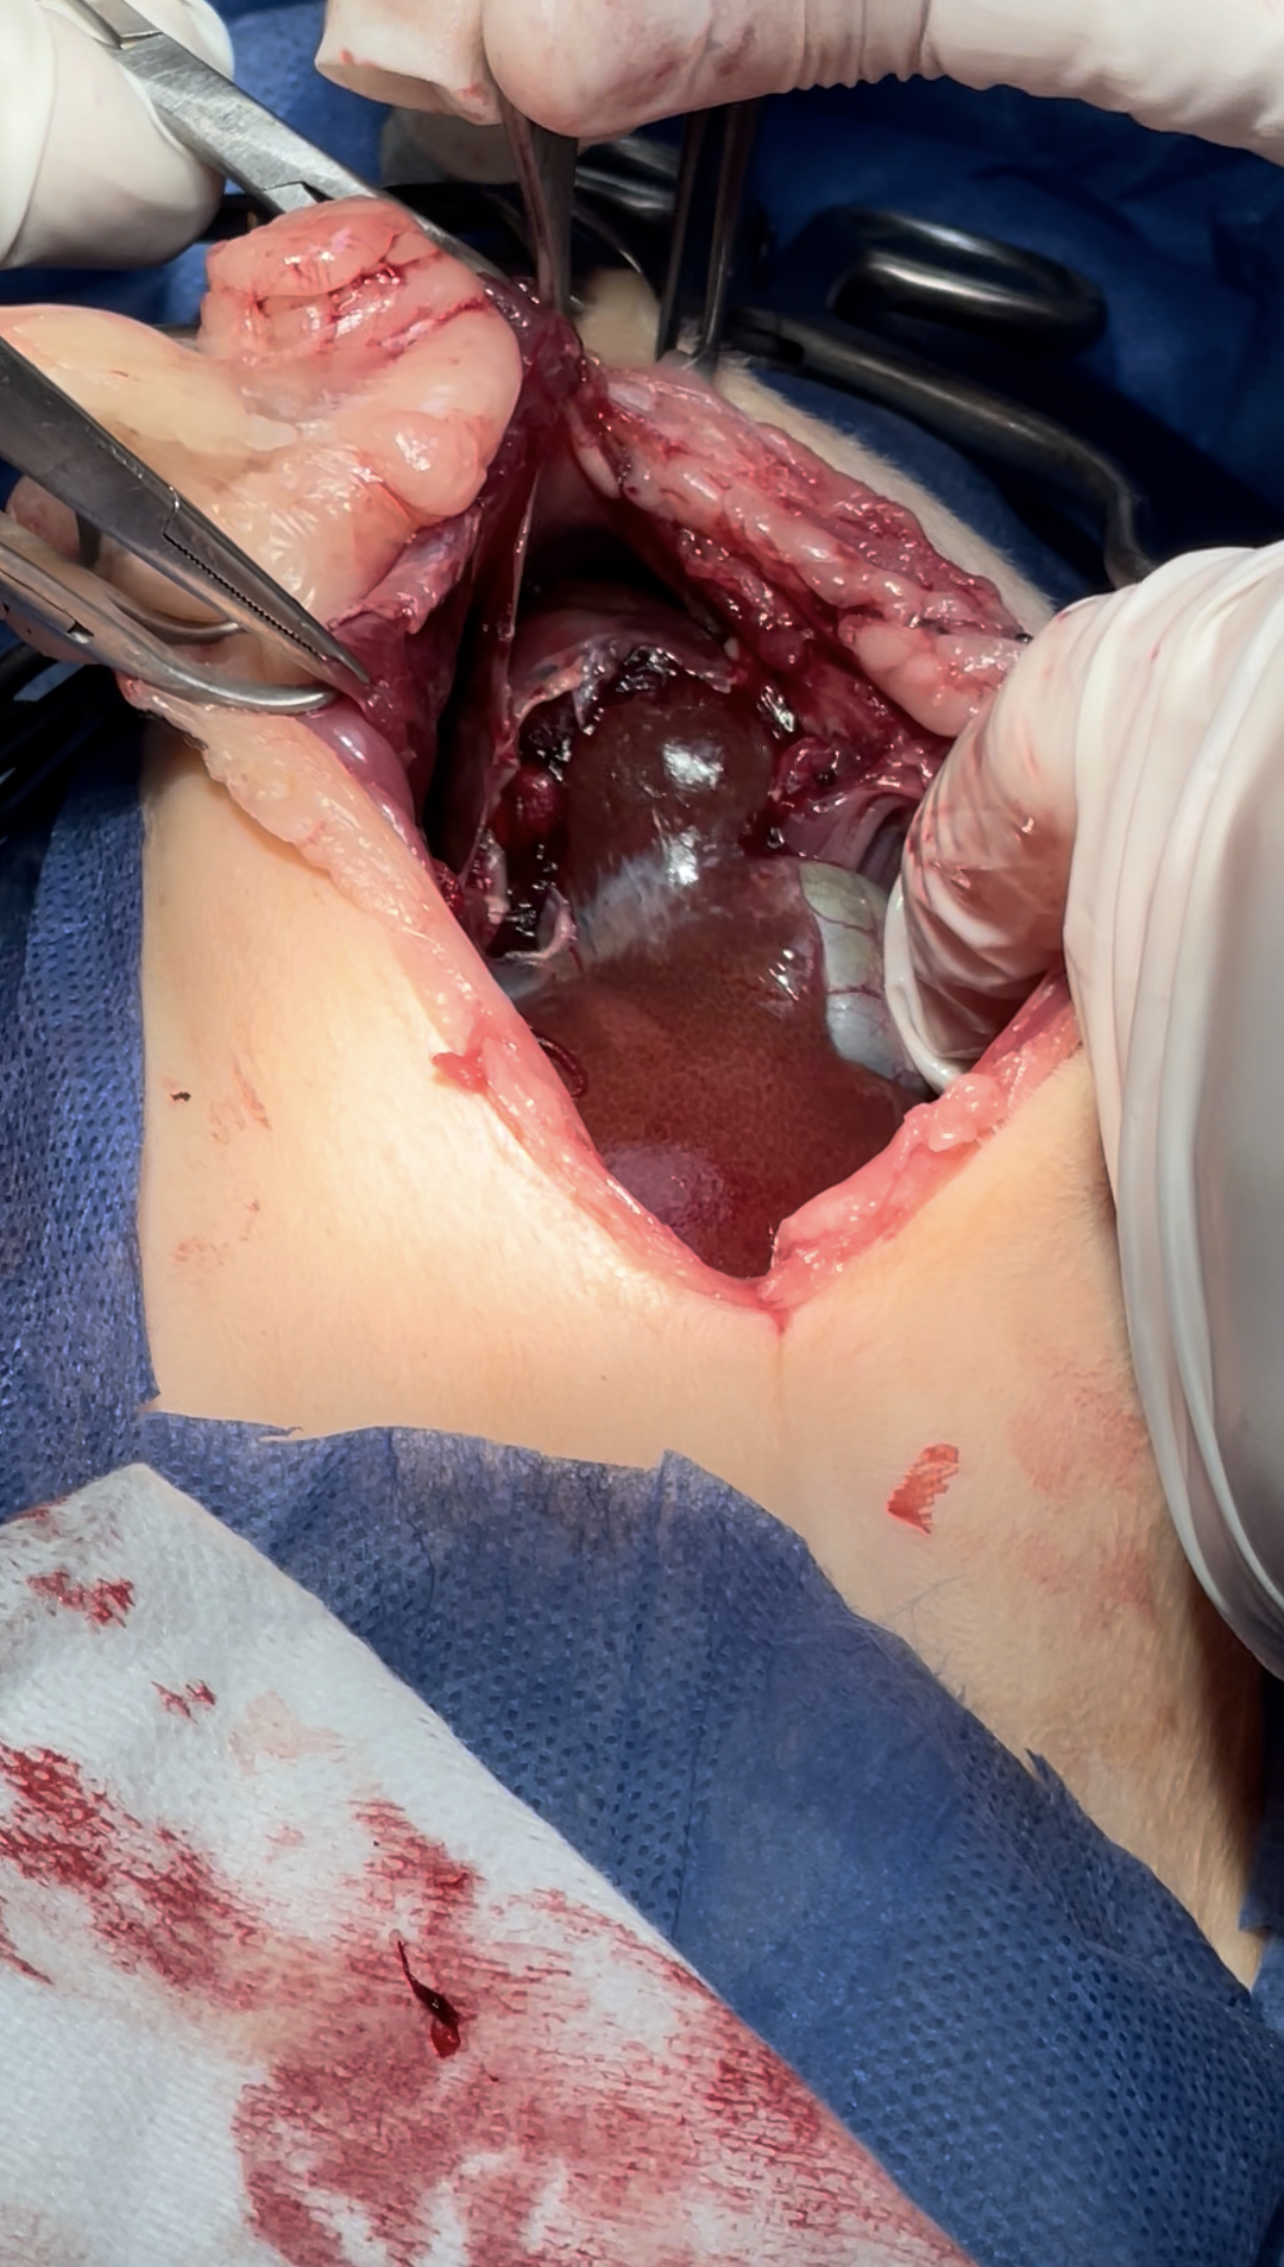

intestines & Liver lobe passing through a narrow hole after being healed over

Dissection of the intraabdominal adhesive part of the live

Widening the herniation to allow organ exteriorization

Lacerations while dissection compressed with Gelfoam to minimize the parenchymal injury